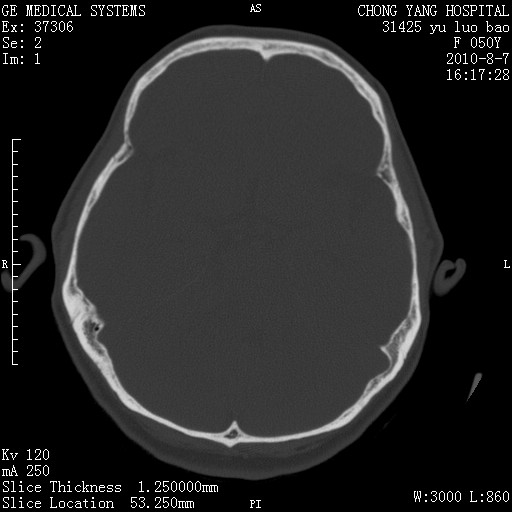

右侧桥小脑角区占位--听神经瘤,建议增强或mri检查。

右侧桥小脑角去等密度占位,右侧内听道扩大、骨质吸收,考虑:右侧听神经瘤,建议增强检查。

考虑听神经瘤可能性大。